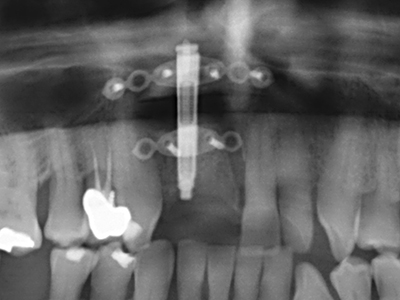

Piezo surgery has additional advantages when harvesting bone blocks. In addition to the high precision with osteotomy described above, the use of the thin saw tips specifically minimizes loss of material. Greater loss of material during harvesting can be expected with the thicker instrument tips, particularly when using Lindemann drills (Lakshmiganthan, Gokulanathan et al. 2012). The basal separation, which is necessary particularly for retromolar block transplants, is simplified by specially designed rectangular saws, with the result that piezo surgery is viewed as a precise, simple and safe procedure for harvesting retromolar bone blocks (Happe 2007) (Fig. 1-12).

Indication: Bone splitting

Bone tissue is not simply a mineral structure but also contains a substantial proportion of collagen fibres. This means it not only has good compressive strength but also a degree of flexibility, which can be taken advantage of when performing bone augmentations. In the classical expansion procedure using bone splitting, the atrophied alveolar ridge is split longitudinally and carefully expanded after reaching an adequate osteotomy depth (Fig. 13-16), ideally without substantial removal of the periosteum (Brugnami, Caiazzo et al. 2014, Stricker, Fleiner et al. 2014). Screw and plate systems with increasing expansion distance have proven effective in separating the two bone lamellae while remaining below the fracture threshold. In general, residual bone widths of at least 3–4 mm are required (Chiapasco, Zaniboni et al. 2006) to guarantee adequate flexibility and sufficient bone coverage of the future implants. If necessary, a vertical relief osteotomy on one or both sides can improve flexibility. A combination with additional augmentation techniques, particularly on the buccal side, has been described as an alternative to the classical technique.

The splitting procedure is particularly atraumatic and there is no significant loss of dimension when using piezosaws, and there are no significant differences between implants in split jaws and implants in an alveolar ridge without a bone deficit (Chiapasco, Zaniboni et al. 2006, Danza, Guidi et al. 2009). However, sufficient continuous irrigation is essential, particularly with locally restricted and deep splitting to prevent thermal stress in the apical osteotomy regions.